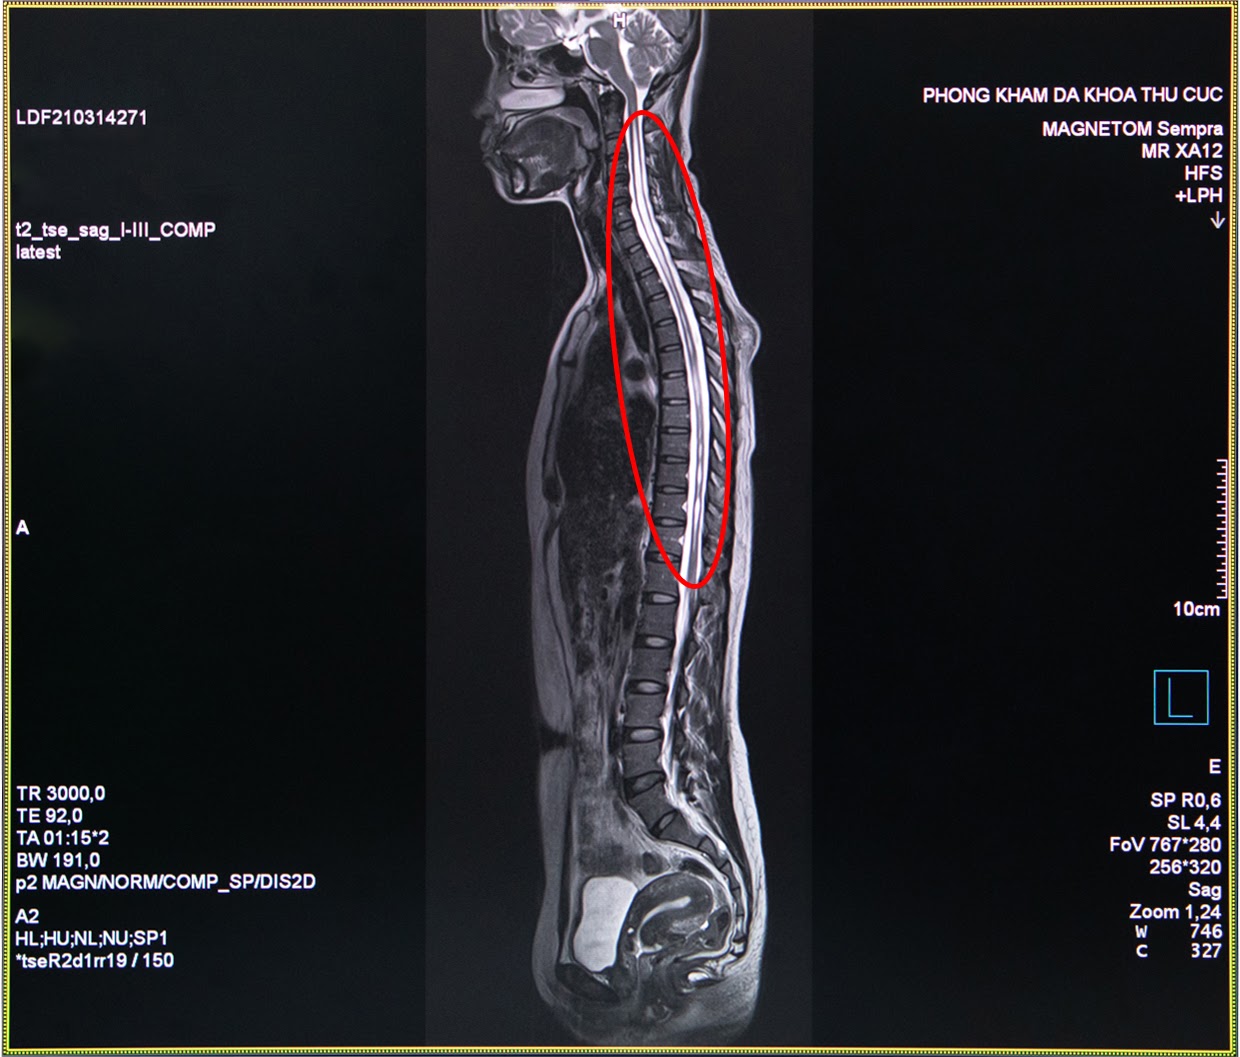

Bác sĩ chẩn đoán hình ảnh Nguyễn Chí Phồn - Phòng khám đa khoa Thu Cúc cho biết: “Trường hợp của chị H. là chụp cộng hưởng tử MRI cột sống và tuỷ sống có tiêm thuốc đối quang từ nhằm phát hiện những tổn thương thần kinh. Đây là công cụ đáng tin cậy nhất để chẩn đoán bệnh rỗng tuỷ sống. Đối với những trường hợp nghi ngờ bệnh nhân bị rỗng tủy sống nếu chỉ định chụp X- Quang hay chụp cắt lớp vi tính MSCT sẽ khó có thể đánh giá chính xác được”.

Hình ảnh thu được từ chụp cộng hưởng từ MRI tủy sống của chị H. cho thấy trong đoạn tủy sống của chị hình thành một hốc rỗng chứa các dịch, các dịch này tích lại thành các khoang và nang hốc đây là biểu hiện của căn bệnh rỗng tủy. Ngay sau khi có kết quả khám cận lâm sàng, các bác sĩ của Thu Cúc đã hội chẩn nhằm xác định căn nguyên bệnh và tìm ra phương pháp điều trị tốt nhất cho chị H.